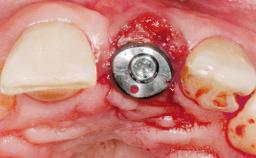

Late Placement of an Implant in a Maxillary Left Central Incisor Site

A 30-year-old female patient had lost tooth 21 and was referred to our clinic for consultation and treatment. Due to advanced apical infection, tooth 21 had been extracted two months earlier at another clinic and an acrylic-resin tooth had been bonded to the adjacent teeth. The patient desired implant treatment to avoid any damage to the adjacent natural teeth. While the patient had no history of any systemic disorder, she was a heavy smoker and exhibited medium to advanced periodontitis in the entire jaw. After the initial treatment to achieve a pocket probing depth of less than 4 mm and no bleeding on probing, a decrease in the height of the papillae mesial and distal to the extraction site and overall gingival recession were observed.

Type of Implants One-Piece|Reduced-Diameter

Bone Augmentation Horizontal|Staged

Augmentation Materials Autogenous chips|Membrane

Soft Tissue Grafting Simultaneous